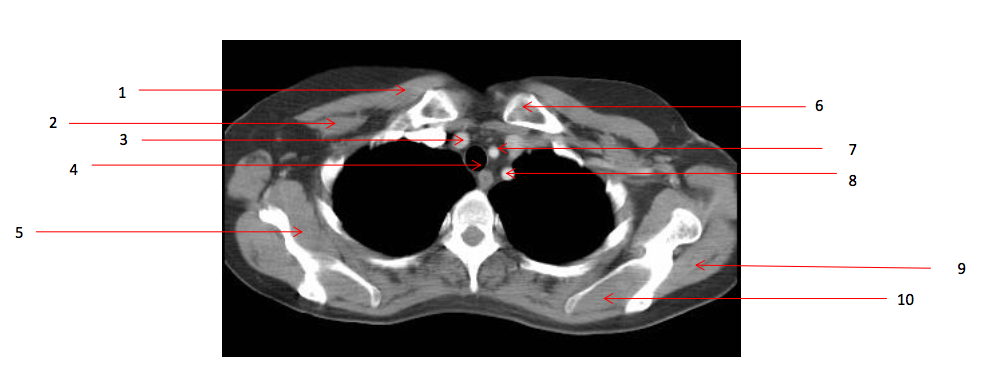

Number 2?

Rt pectoralis minor muscle

Number 6?

Lt clavicle

Number 10?

Lt supraspinatus muscle

Number 1?

Rt pectoralis major muscle

Number 8?

Lt subclavian artery

Number 4?

Trachea

Number 7?

Lt common carotid artery

Number 5?

Rt subscapularis muscle

Number 9?

Lt infraspinatus muscle

Number 3?

Brachiocephalic artery